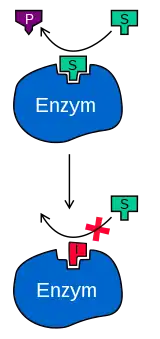

Metabolic enzyme disorders hinder conjugation to varying degrees. Gilbert Syndrome, a hereditary disease affecting 5% of the US population, leads to stress-induced mild hyperbilirubinemia.[9] The mutated UGT1 gene produces defective UGT1A1 enzymes vital for bilirubin conjugation.[20]

This pathology is shared by another genetic disorder, Crigler-Najjar syndrome, which is subdivided into two types: type 1 (CN-1) and type 2 (CN-2), with the former displaying complete UGT1A1 enzyme activity loss and the latter only partially affected. Thus, unlike CN-1 displaying lifelong persistent jaundice, CN-2 shows milder symptoms and may escape diagnosis until adulthood.

Dubin-Johnson syndrome and Rotor's syndrome, both rare hereditary metabolic defects characterized by synthesis of faulty proteins responsible for exporting conjugated bilirubin out of hepatocytes, are responsible for majority of isolated hyperbilirubinemia.[22] Dubin-Johnson syndrome is associated with ABCC gene mutations, creating insufficient functional MRP2 transporters for bilirubin excretion.[23] Rotor syndrome is caused by homozygous SLCO1B1 and SLCO1B3 gene mutations which instruct production of OATP1B1 and OATP1B3 on hepatocyte membrane mediating uptake of bilirubin glucuronide from plasma.[24] Innate shortage of MRP2, OATP1B1 and OATP1B3 in these two diseases lowers bilirubin removal efficiency, causing hyperbilirubinemia.

Drug-induced cholestasis is an adverse outcome of drug-induced-liver-disease.[25] Mechanisms other than direct hepatocyte injury includes competitive inhibition by drug metabolites, such as troglitazone metabolites, that outcompete bilirubin for MRP2 transporters for secretion.[26]